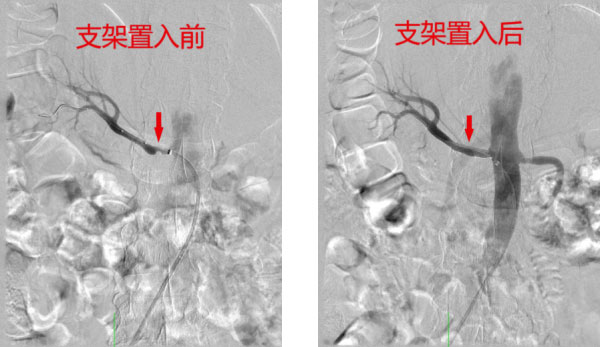

3. 手术治疗:肾动脉支架血管成形术,肾动脉内膜切除术,旁路搭桥术及自体肾移植术。